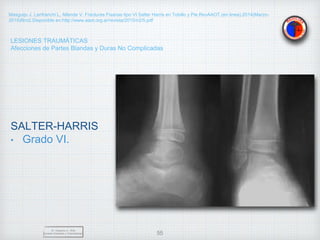

SALTER-HARRIS

• Grado VI.

Ablación del anillo pericondral,

Origen Traumático(Perdida de sustancia).

Deformante y Discapacitante.